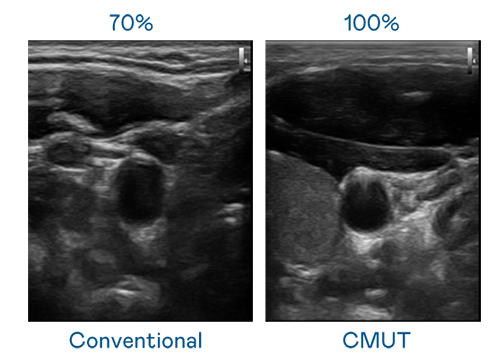

CMUT 技术是一种用电容式微机电元件来产生超音波讯号的技术。与传统 PZT 压电式技术相比,CMUT 频宽增加 30%,更宽频的超音波讯号让影像解析度大幅提升,是实现高影像品质医疗超音波扫描、促进精准医疗发展的关键技术。

大频宽带来超清晰影像

超音波影像的解析度高低,首先取决于探头能发出的讯号频宽。AG真人 CMUT 可提供高清晰的超音波讯号,提供高频宽、高灵敏度、影像纹理细节更高的超音波影像,协助医护人员缩短影像判读时间及利用精准的医疗影像进行诊断。